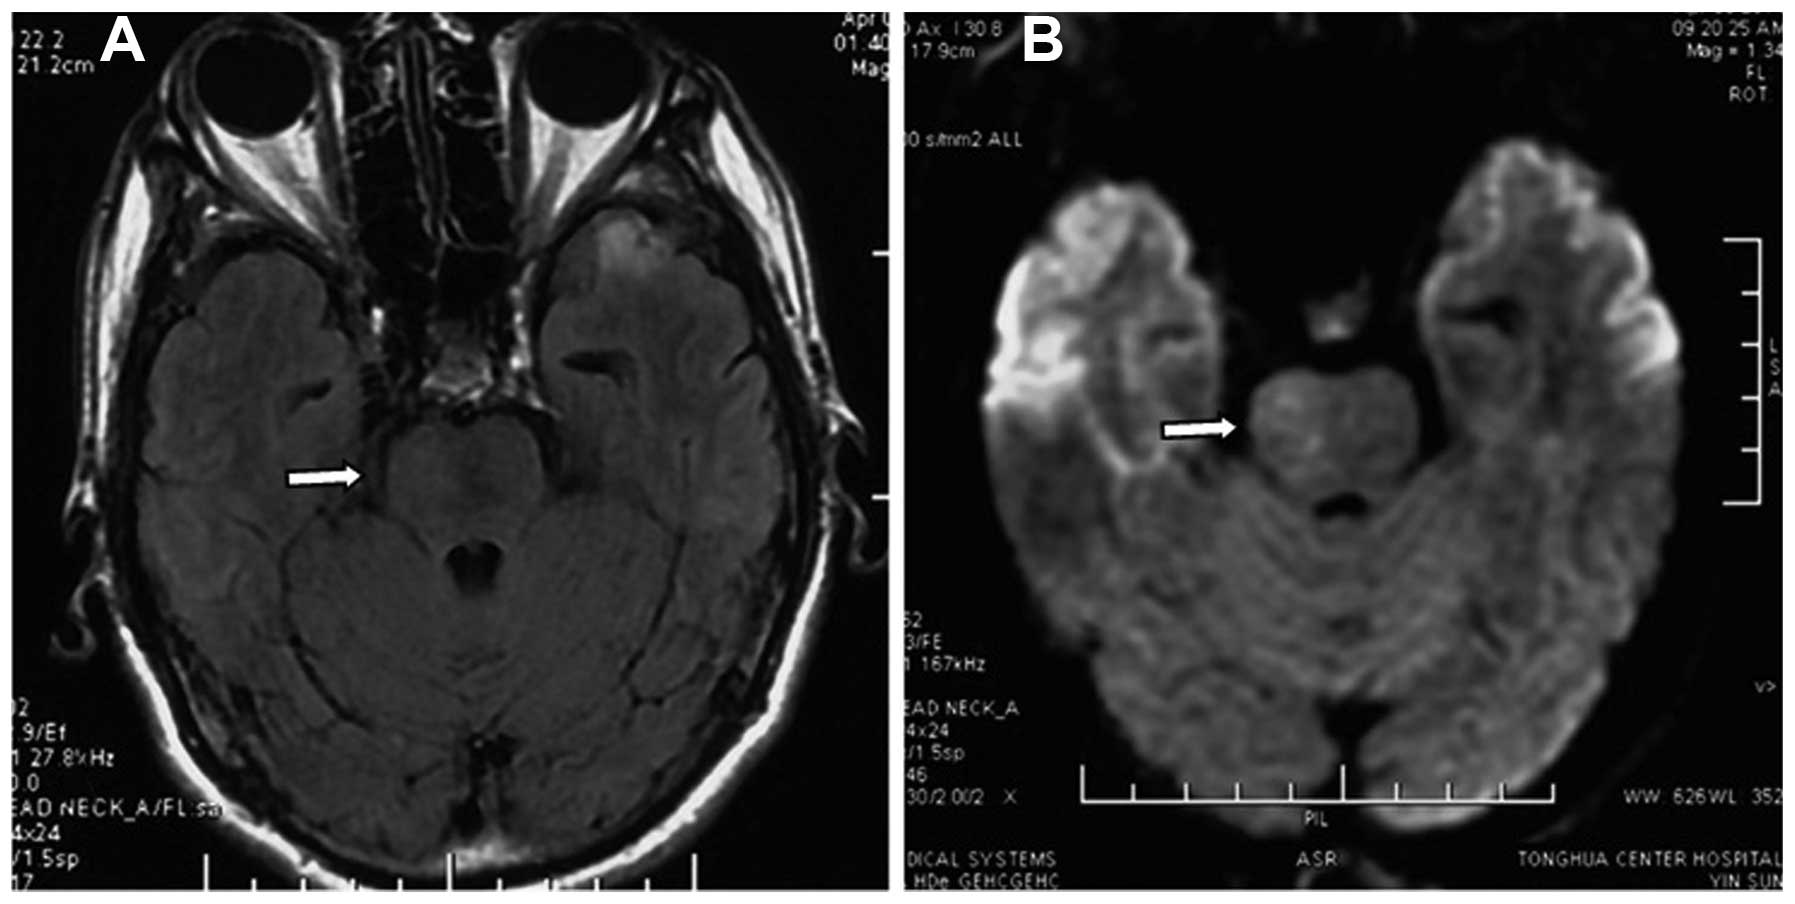

Brainstem edema caused by traumatic carotid-cavernous fistula (TCCF) is rare, and there is little information available regarding its clinical characteristics. The present report describes the case of a 51‑year‑old man with TCCF, who presented with right exophthalmos and intracranial bruit for 1 week. One month prior to admission at hospital, he fractured the frontal and ethmoid sinuses. Digital subtraction angiography confirmed the diagnosis of TCCF, and magnetic resonance imaging (MRI) suggested edema on the right side of the pons. Five days after admission, the patient exhibited left hemiparesis, and MRI revealed aggravation of the brainstem edema. Following treatment with transarterial balloon embolization, the clinical symptoms, including hemiparesis, were relieved; at the 1‑month follow‑up, the brain edema had disappeared. The patient was normal at the 6‑month follow‑up. Following the report of the present case, we reviewed six additional cases previously reported in the literature and discussed the potential mechanisms of TCCF‑associated brainstem edema. We conclude that occlusion of the superior petrosal sinus may contribute to brainstem edema caused by TCCF. Relief of the brainstem edema and brainstem edema‑associated clinical symptoms can be achieved with transarterial coil or balloon embolization of the TCCF to reduce the drainage pressure in the brainstem veins.

Figure 3